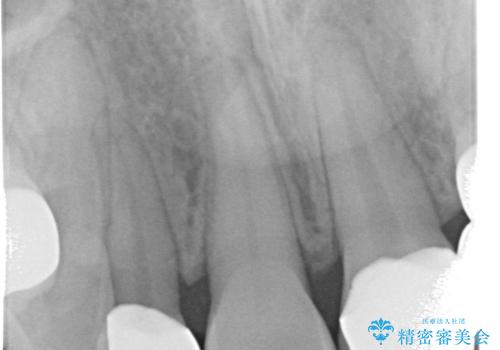

- 歯列矯正後に前歯にブリッジを入れた方の経過です。

矯正治療の術前後の経過は以下をご覧ください。

矯正治療で歯の位置を整えてからブリッジを入れると歯の幅を自由に設定できるため、左右対称にできます。結果矯正なしでいきなりセラミックにする場合と異なり、無理に角度を変えたりする必要がなく、神経をなるべく温存したまま審美的なセラミック治療が行えます。